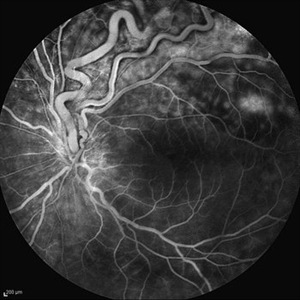

Behcet's Disease Behcet's DiseaseMar 13 2013 by Hamid Ahmadieh, MD Mid phase FA of the right eye of a 23-year-old man with retinal vasculitis and branch retinal vein occlusion (BRVO) due to Behcet's disease . Photographer: Solmaz Shahmohammad, Negah Eye Center, Tehran Imaging device: Heidelberg Spectralis Condition/keywords: branch retinal vein occlusion (BRVO), retinal vasculitis

Behcet's Disease Behcet's DiseaseMar 13 2013 by Hamid Ahmadieh, MD Late phase FA of the right eye of a 23-year-old man with retinal vasculitis and branch retinal vein occlusion (BRVO) due to Behcet's disease . Photographer: Solmaz Shahmohammad, Negah Eye Center, Tehran Imaging device: Heidelberg Spectralis Condition/keywords: branch retinal vein occlusion (BRVO), retinal vasculitis